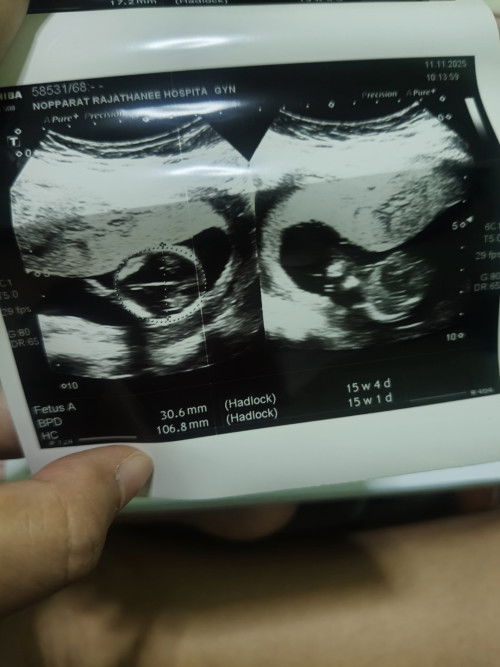

กำหนดคลอด 8 พฤษภาคม 69 วันนี้มาโรงพยาบาลรัฐ ตรวจครรภ์ตามนัด พยาบาลนับอายุครรภ์ 16 + 2. แต่ในแอป 16 + 6 อันนี้จะเป็นอะไรไหมคะ พยาบาลให้ฟังเสียงหัวใจ แต่ไม่ค่อยได้ยิน เลยเปลี่ยนเป็นอัลตร้าซาวด์ พยาบาลบอกว่าเห็นหัวใจแต่ที่ไม่ค่อยได้ยินเพราะอายุครรภ์ยังน้อย แบบนี้ปกติใช่ไหมคะ #ขอคำแนะคำปรึกษาคะ #ท้องแรกกังวนมากค่ะ#ขอบคุณสำหรับคอมเม้นล่วงหน้าค่ะ #ท้องแรกท้องเล็ก